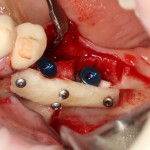

Остеопластические операции: факторы успеха. Часть II.